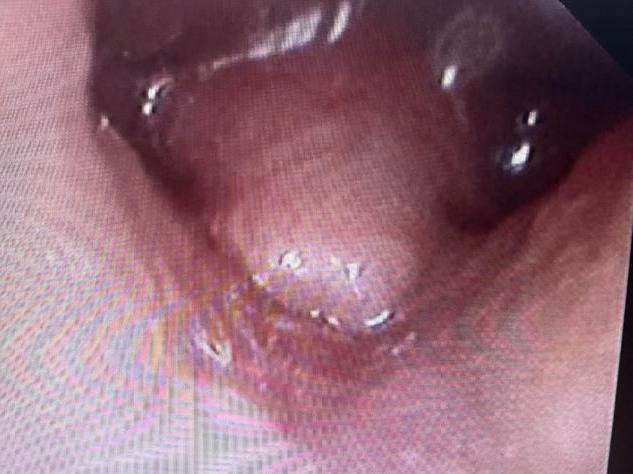

岳阳市中医医院儿科主任雷东方接诊患儿时,根据家长的描述,认真细致地听诊、体查后,认为宝宝发出的“呼噜呼噜”的声音,可能是喉软骨软化症。随后排纤支镜检查。果不其然,患儿镜下会厌软骨明显软化、卷曲、倒伏,证实了这一诊断。

↑↑↑正常(左)与喉软化症(右)对比图↑↑↑